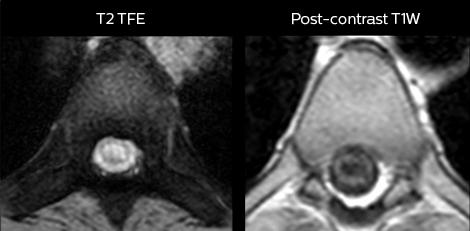

„mDIXON TSE wird in unserer Notaufnahme ausgiebig für die Wirbelsäulenbildgebung eingesetzt“, führt Dr. Karis aus. „Besonders vorteilhaft ist, dass dieses Verfahren im Hinblick auf suszeptibilitätsbezogene Probleme sehr stabil ist, die häufig bei klassischen spektralen, fettgesättigten Bildern auftreten. Im Wesentlichen treten derartige Probleme beim mDIXON-Verfahren überhaupt nicht auf. Wir sind wirklich froh, in unserer Notaufnahme über die fettfreie Bildgebung des mDIXON-Verfahrens zu verfügen.“

„Für die routinemäßige, kontrastmittelfreie Untersuchung der Brust- und Halswirbelsäule führen wir zum Beispiel eine mDIXON T2-TSE-Sequenz durch, die uns zwei Ergebnisse liefert: die T2-gewichteten Bilder auf Fett- und Wasserbasis sowie die sagittalen T2-gewichteten Bilder auf reiner Wasserbasis. Anschließend erfolgt noch eine axiale Gradientenecho-Untersuchung.“